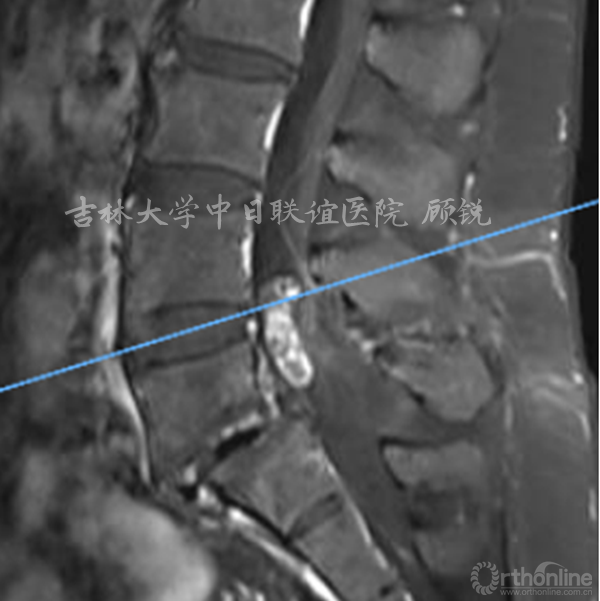

增强MRI增强如下:

腰椎增强MRI示:

占位组织强化明显为实质病变,依据瘤体与硬膜间呈锐角;T1W1:等信号;T2W1:混杂高信号STIR:环状增强,Non-enhancement area(+)。经科内会诊该患者的诊断为:峡部裂型腰椎滑脱(L5 Ⅱ度)、腰椎管内占位性病变(神经鞘瘤?)。Ozawa H, Aizawa T, Kanno H.Epidemiology of surgically treated primary spinal cord tumors in Miyagi, Japan.Neuroepidemiology. 2013;41(3-4):156-60

CT可以很好的显示骨性结构,但对于椎管内病变、神经组织显示欠佳。MRI可以很好的显示神经、肌肉及椎管内异常,应作为脊柱外科疾病诊疗的常规检查,对椎管内疑有占位性病变的需进一步行增强扫描; MRI上总结出的一些影像学特点可以帮助术前预判肿瘤的性质,预判手术难易程度,协助更好地进行术前计划。